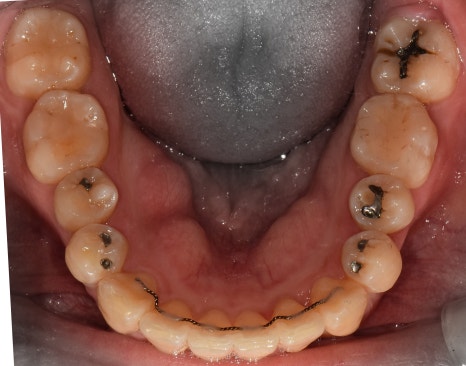

측면에서는 크게 2가지를 느낄 수 있습니다.

- 전치부 치아들의 치축, 전방 뻐드러짐

- 1치대 1치의 관계

*정상이라면, 1치대 2치의 관계를 가져야 됩니다.

또한, 측절치 및 송곳니의 총생들도 같이

관찰을 할 수 있습니다.

앞서, 1치대 1치 관계에 있던 교합관계들이

1치대 2치의 관계로 바뀐것을 볼 수 있으면서

길쭉하게 느껴졌던, U shape 형태의 악궁이

딱 보기 좋은, U shape 로 바뀌었죠.